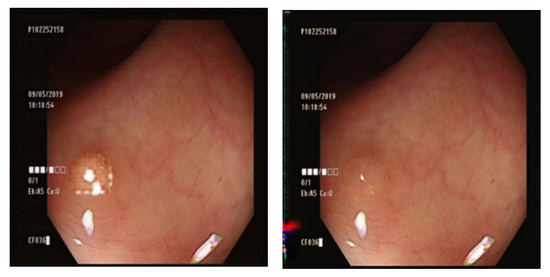

4.1. Comparison of GAN-Generated Images

3.7. Comparison of GAN Output